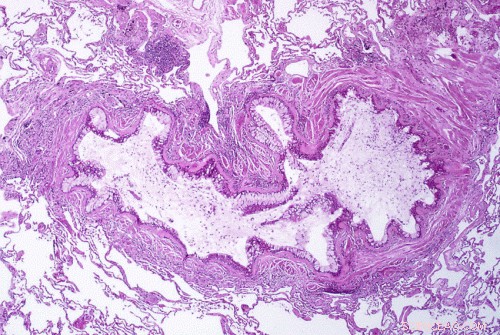

Obstruction of the lumen of a bronchiole by mucoid exudate, goblet cell metaplasia, and epithelial basement membrane thickening in a person with asthma. Credit: Yale Rosen/Wikipedia/CC BY-SA 2.0